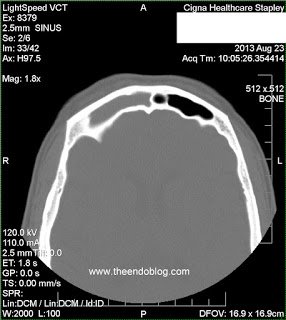

This patient presented to Arizona Sinus Center for evaluation of chronic sinus issues. She presented with chronic, unilateral nasal and facial symptoms, along with foul smelling nasal discharge. Nasal endoscopy was performed and findings include:

- RADIOGRAPHIC FINDINGS:

Endodontic diagnosis, including CBCT, determines that tooth #2 has a prior root canal with a root fracture and extraction is recommended. Tooth #3 has a prior RCT with apical abscess – caused by a missed MB#2 canal during the initial root canal treatment. Retreatment of the root canal #3 is recommended.